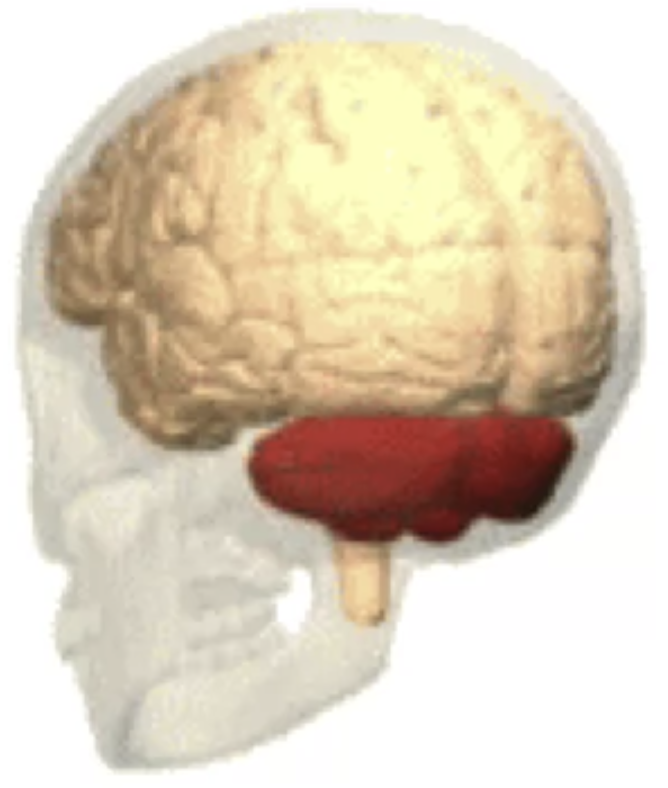

Subcortical Regions

AKA “reptilian brain”, we share this structure with reptiles.

- Medulla - heart rate and blood pressure, basic house keeping

- Pons - regulates sleep cycle and alertness

- Midbrain - sex and aggression

- Cerebellum - regulates the smooth movement

- Corpus callosum - major connection between the two spheres

- Amygdala - our “spider sense”, constantly looks for danger, the brain structure that flips the “switch” for fight or flight response

- Hippocampus - episodic memory, also memorizes what just happen right before the danger